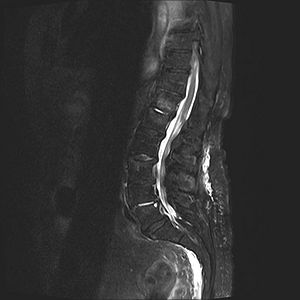

Spinal liquorfistel

MR af spinalkanalen for at identificere duralækagen.